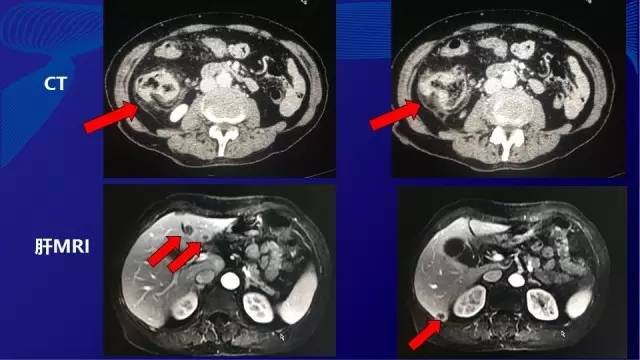

● 急诊CT示:右半结肠占位病变,肝内多发低密度灶

● 2014-11复查肝脏MRI,肝内转移灶增多,增大

● 2014.11 患者自行就诊于介入科,要求行肝脏肿瘤消融术,将肝左外叶(2枚)与右肝(1枚)转移灶进行微波消融,其余病灶(新发两枚)未处理